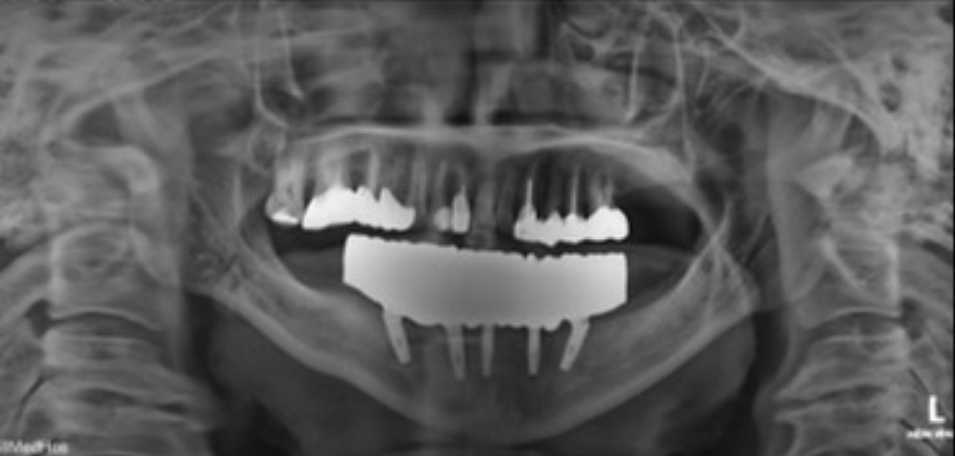

Fig. 1.

Atrophy of mandibular posterior bone is examined by pre-operative intraoral photograph. A. Maxillary occlusal view. B. Frontal view. C. Mandibular occlusal view.

본 증례는 44세 여환으로, 하악 의치가 계속 탈락하여 재제작을 원한다는 주소로 내원하였다. 상악은 고정성 수복물, 그리고 하악은 총의치를 착용 중이었고 하악 양측 구치부의 심한 골 흡수로 인해 유지력 소실로 불편감을 호소하였다. 3개월 전 하악 양측 견치를 발거한 이후로 하악 국소의치를 총의치로 전환하였고, 총의치는 구치부의 심한 교합면 마모와 의치의 후방부가 후구치 삼각 융기를 피개하지 않는 형태였다. 전신 병력으로는 지적장애 및 골관절염으로 약 2개월 간 약물 복용 중이었다. 상악 우측 제1대구치와 제2대구치, 제1소구치 그리고 제2소구치는 우식이 진행된 상태였고, 우측 제2소구치와 우측 제1대구치는 근관치료가 완료된 후 수복되지 않은 상태였다. 상악 좌측 제1소구치와 제2소구치, 그리고 제1대구치 수복물 하방으로 이차 우식이 진행된 상태였고, 전체적으로 교합평면이 균일하지 않은 형태였다(Figs. 1-3).상악 우측 구치부의 수복되지 않은 치아와 상악 좌측 보철물 하방의 이차 우식이 있는 치아는 모두 우식 제거가 필요하여 양측 구치부 각각 3개의 치아는 재수복을 결정하였고, 하악은 구치부의 심한 치조골 흡수로 인해 의치 사용은 불가할 것으로 판단하여 전방부에 임플란트를 식립하여 구치부는 캔틸레버 형태를 가지는 all-on-X 수복을 계획하였다. 의치의 수직고경에 맞춰 교합 평면을 균일하도록 하여 왁스업 시행하였고(Fig. 4), 이후 적절한 교합 수직 고경의 임시 의치를 제작하였다. 약 2개월의 적응기간을 거쳐 의치 적응도와 수직 교합 고경을 평가하였고 적절한 기능과 심미를 확인하였다. 상악 우측 제1소구치와 제2소구치, 제1대구치 그리고 상악 좌측 제1소구치와 제2소구치, 제1대구치는 우식을 제거한 다음, 임시 보철물로 재수복하여 적절한 교합 평면을 설정하였다(Fig. 5).환자가 적응한 임시 의치를 모델 스캔(Medit T710, Medit, Seoul, Korea)하여 프린팅용 레진(Graphy Tera Harz SG-100, Graphy, Seoul, Korea)을 이용하여 3D 프린팅하였고, 출력된 의치에 방사선 불투과성 레진(G-æenial Universal Flo, GC, Luzern, Swiss)을 부착하여 레진 마커를 형성하였다. 레진 마커를 부착한 프린팅 의치를 장착한 채로 콘빔 전산화 단층촬영(CBCT, R2 Studio Q, Megagen, Seoul, Korea)를 촬영하였다(Fig. 6). 촬영한 CBCT 데이터와 의치 스캔 파일을 중첩하여 CAD 소프트웨어(R2 Studio Q, Megagen, Seoul)를 통해 이상적인 임플란트 식립을 계획하였다. 전후방 거리를 연장하여 적절한 캔틸레버를 부여하기 위해 전방부에 3개의 임플란트를 식립하고, 양측 후방부에는 약 30도 경사진 임플란트를 식립하도록 계획하였다(Fig. 7).가이드는 상악의 자연 치열과 대합되는 의치 복제 형태의 상부 가이드, 그리고 가이드 핀이 존재하는 하부 가이드로 이루어지도록 디자인되었다(Fig. 8). 상부 가이드는 임시 의치의 스캔 데이터를 이용해 상부 가이드의 하부면과 하부 가이드의 상부면이 장착되어 구내에서 적합될 수 있도록 CAD 소프트웨어(Meshmixer, Autodesk, San Francisco, CA, USA) 상에서 디자인되었다. 임시 의치의 하부면과 하부가이드의 하부면을 치은과 중첩시켜 어버트먼트의 위치에 홀을 형성한 다음 3D 프린팅(Graphy Tera Harz SG-100, Graphy, Seoul, Korea) 하였다. 수술 당일 장착될 임시 보철물 또한 동일한 CAD 소프트웨어를 통해 제작하였다.수술 당일 이중 가이드를 구내에 장착하여 하부가이드를 고정 핀으로 고정시킨 후(Fig. 9), 계획된 위치에 임플란트 고정체를 식립하였다. 임플란트는 5개 모두 외부 연결형 고정체(AnyOne External, Megagen, Seoul, Korea)를 사용하였고, 식립 시 식립 토크는 모두 40N 이상, ISQ는 70이상으로 양호한 초기 고정력을 확보하였다(Fig. 10). 즉시 부하를 위해 기성 어버트먼트를 체결하였고, 임시 보철물을 장착하여 양측 소구치부에서의 균일한 교합을 확인하였다(Fig. 11).임플란트 주위 골과 치은의 회복을 위해 약 2달간 임시 보철물을 경과 관찰하였고, 이후 최종 보철을 위한 인상 채득을 시행하였다. 상하악 임시 보철물을 장착한 중심교합 상태에서 구내 스캔(Trios 4, 3 Shape, Copenhagen, Denmark)을 시행하여 악간 관계를 채득하였다(Fig. 12). 임시 보철물을 제거한 상태에서 하악의 전방부 3개의 임플란트에 scan body(Scan Abutment, Megagen, Seoul, Korea)를 연결하고, 양측 최후방 임플란트 2개에는 각각 Ti base multi-unit abutment(multi-angled abutment, Osstem, Seoul, South of Korea)를 30Ncm으로 체결한 후 multi scan body(TS Multi scanbody, Osstem, Seoul, Korea)를 연결하여 구내 스캔(Trios 4, 3Shape, Copenhagen, Denmark)을 시행하였다. 이후 스캔 바디를 연결하여 채득한 스캔 파일을 상하악 임시 보철물 상태에서 채득한 스캔 파일과 중첩하여 CAD 소프트웨어(exocad GmbH, Darmstadt, Germany)에서 최종 보철물을 디자인하였다(Fig. 13).최종 보철물은 양측 최후방 임플란트 고정체에 각각 Ti-base(TS multi Ti base, Osstem, Seoul, Korea)와 접착된 나사 유지형 단일 지르코니아 크라운으로, 지르코니아 블록(Zircen, Kuwotech, Gwangju, Korea)을 밀링하여 제작하였고, 치경부 하방으로 포세린으로 치은 형태를 부여하였다. 전방부 3개의 임플란트 고정체에는 맞춤형 지대주를 제작하여 30N으로 체결하였고, 양측 최후방 고정체는 20Ncm으로 체결한 후 레진 시멘트(Rely X U200; 3M ESPE, St. Paul, MN, USA)로 접착 시행하였다. 장착 후 중심교합시 양측의 제1대구치 부위에서 교합력이 적게 가해지도록 교합 조정 시행하였으며, 전방과 측방운동시에 임플란트 상호보호교합이 되도록 조정하였다. 또한 연결부 하방으로 치실을 통과시켜 치은 점막 사이 공간을 평가하였으며, 구강 위생 관리의 용이성을 확인하였다. 이후 1주, 1개월, 3개월 경과 관찰하였고, 환자는 저작이나 심미, 발음 등에서 만족해하였다(Figs. 14 and 15).